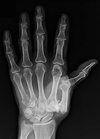

A 59-year-old woman comes for evaluation because of a 7-month history of pain over the radial aspect of the right wrist that is aggravated with forceful gripping. She denies any history of trauma to the hand or wrist. On physical examination, there is tenderness to palpation over the right anatomic snuffbox and thenar eminence. Axial load and shifting of the basal joint does not result in crepitance or pain. Resisted thumb extension at the metacarpophalangeal joint level is not painful. An x-ray study of the wrist is shown. Which of the following is the most appropriate operative management?

The correct response is Option A.

Scaphotrapeziotrapezoid (STT) arthritis can often be misdiagnosed on initial presentation as basal joint arthritis. The keys to differentiating the two sites of pain include physical examination, which shows tenderness more proximal than the basal joint and absence of pain with a grind maneuver, coupled with imaging showing osteoarthritic degeneration at the STT rather than the trapeziometacarpal level. Treatment for the arthritic pain can consist of resection arthroplasty or arthrodesis. Both techniques can provide good relief of symptoms. Resection arthroplasty often is used when the scapho-trapezoid articulation is relatively preserved. Regardless of technique chosen, the surgeon should address both the scapho-trapezial and the scapho-trapezoid joints during the procedure.